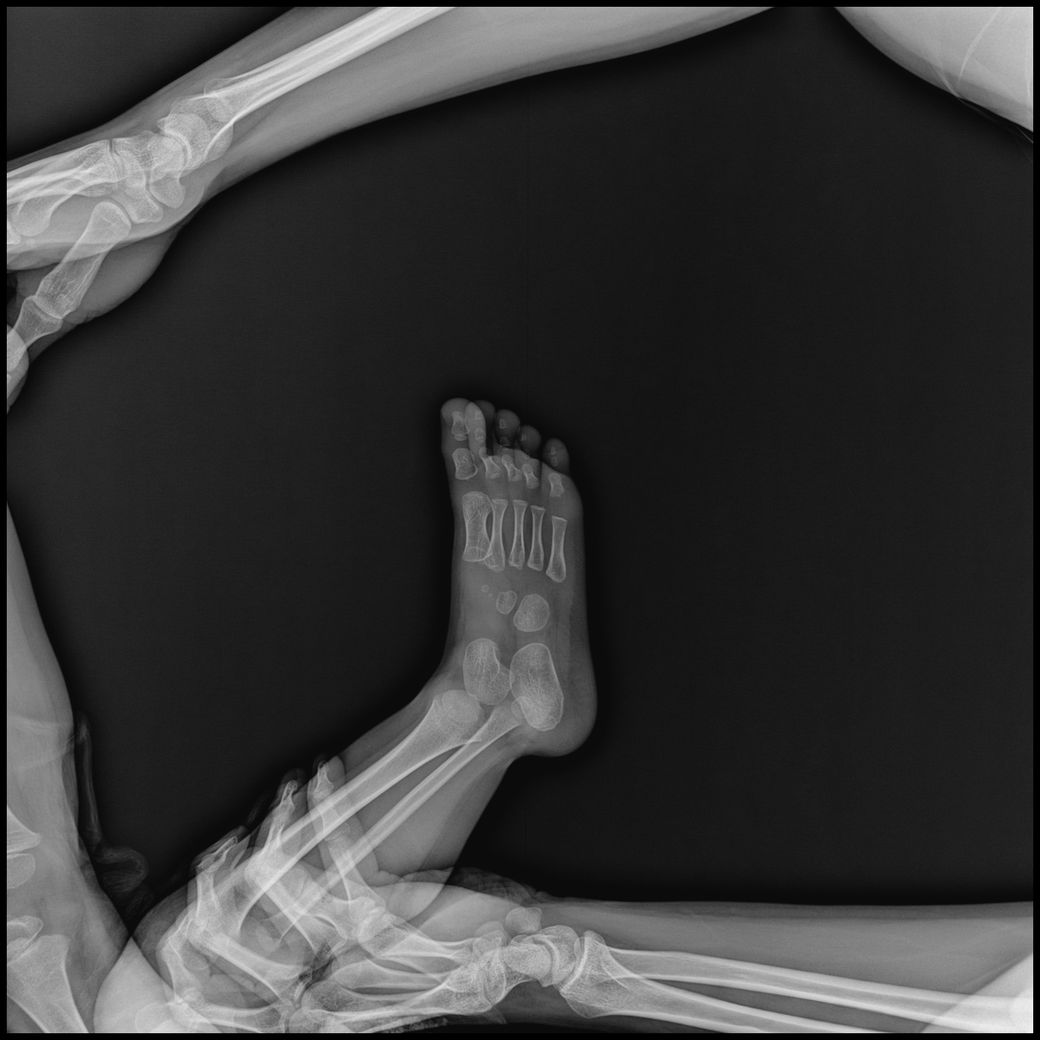

• 3번 째 사진

- 발~다리사진 : 10장